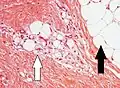

Lipoblasts (white arrow) and lipocytes (black arrow), in a case of lipoblastoma

Lipoblasts (white arrow) and lipocytes (black arrow), in a case of lipoblastoma -